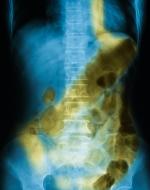

The process of digestion involves physical and chemical changes to the food

57584443

we eat.